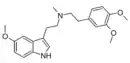

| 5-MeO-34MPEMT [3] | artificial | 5-OCH3 | CH3 | CH2CH2C6H3(p,m-OCH3) | N-methyl-N-[2-(3,4-dimethoxyphenyl)ethyl]-2-(5-methoxy-1H-indol-3-yl)ethanamine | |